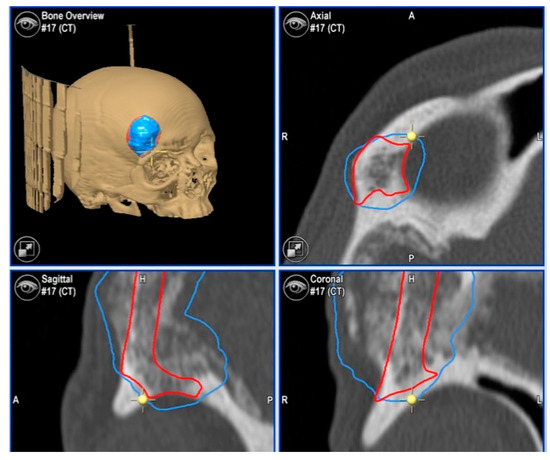

2.3.1. Virtual Surgical Plan

2.3.3. Surgical Navigation